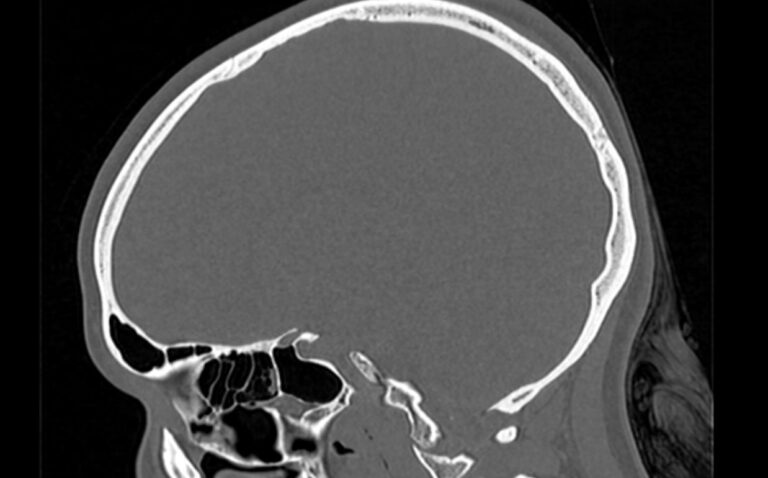

Мультиспиральная компьютерная томография является наилучшим методом диагностики патологии костей черепа. В основе методики лежит использование рентгеновского излучения с последующей цифровой обработкой полученных данных и получения трехмерных реконструкций изображений.

Костная ткань отличается высокой плотностью и способна в большой степени поглощать рентгеновские лучи. Поэтому на послойных снимках, полученных при проведении мультиспиральной КТ черепа можно детально рассмотреть свод черепа, кости лица, основание черепа. Это позволяет с наибольшей точностью визуализировать различные объемные образования, такие как остеомы, дифференцировать фиброзную дисплазию или костные метастазы. Преимуществами методики КТ является отличная визуализация костных структур, быстрота выполнения процедуры и доступная цена. Все это делает КТ незаменимой при диагностике травматических повреждений (например переломов основания черепа или орбит), аномалий развития, при планировании оперативных вмешательств.

В нашей клинике КТ черепа выполняется на современном оборудовании, представленном мультиспиральными томографами последнего поколения TOSHIBA AQUILION. За счет увеличенного количества сверхчувствительных детекторов аппараты обеспечивают высокое качество изображений, что способствует проведению точной и достоверной диагностики. При этом пациент получает минимальную дозу облучения.